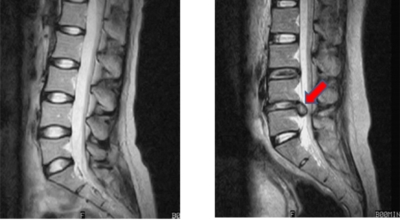

디스크는 일어선 상태에서는 중력을 받아 납작해져서 바깥쪽으로 약간 볼록한 형태가 된다고 합니다. 디스크는 그 특수한 구조 때문에 웬만한 힘이 가해져도 효율적으로 쿠션 역할을 할 수 있겠습니다. 그러나 급작스럽게 무거운 물건을 들어 올리거나, 부자연스러운 자세를 오랜 시간 취하면 디스크에 무리한 힘이 가해지면서 디스크가 밖으로 돌출이 되게 돼요. 심한 경우 디스크를 감싼 막이 터지면서 그 안에 있는 수핵이 튀어나오게 돼요.

디스크는 대개 후방이나 후외방으로 돌출되는데 이때 바로 곁에 있는 신경을 누르게 된다고 합니다. 돌출된 디스크는 척추의 어느 부위에나 일어날 수 있어요. 목에 생기면 '목 디스크', 등에 생기면 '등 디스크', 허리에 생기면 '허리 디스크'라고 부른다고 합니다.

이와 같이 디스크가 돌출되어 신경을 눌러 요통 또는 다리가 아프고 저린 증상을 유발하는 병을 '추간판 탈출증' 및 '디스크 탈출증'이라고도 불러요. 발생 빈도별로 보면 허리 디스크가 가장 흔합니다. 그다음이 목 디스크이지요. 등 디스크는 드문 병이라고 합니다.